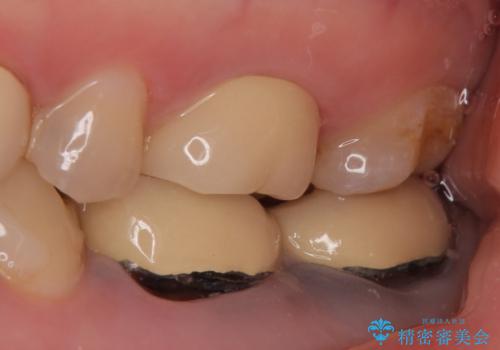

- 右下奥歯の歯茎がよく腫れるので診て欲しいといらっしゃった方の症例です。

診査の結果、右下6番目の根尖病変を認めたため再根管治療を行いました。

また右下7も根管充填が不十分なため再根管治療を行いました。

症状の消失を確認後、オールセラミッククラウンによる補綴を行いました。